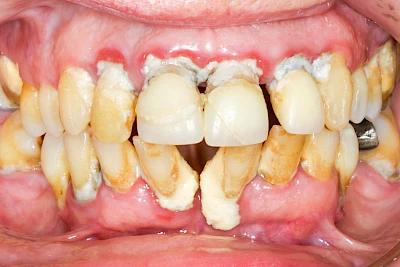

Ist zunächst nur das Zahnfleisch von der Entzündung betroffen, spricht man von Gingivitis. Später, wenn auch der Knochen um die Zähne herum entzündet ist, spricht man von einer Parodontitis. Bei der Parodontitis wird der Knochen nach und nach abgebaut und das Zahnfleisch zieht sich zurück. Die Zahnhälse und Zahnwurzeloberflächen liegen mehr und mehr frei. Die Zähne werden zunehmend lockerer und fallen schließlich aus.

Bei Implantaten – also operativ eingebrachten künstlichen Zahnwurzeln – kann der Körper die Bakterien auch nicht so gut abwehren. Hier spricht man im Fall einer Entzündung von einer Peri-Implantitis, also einer Entzündung um das Implantat herum.